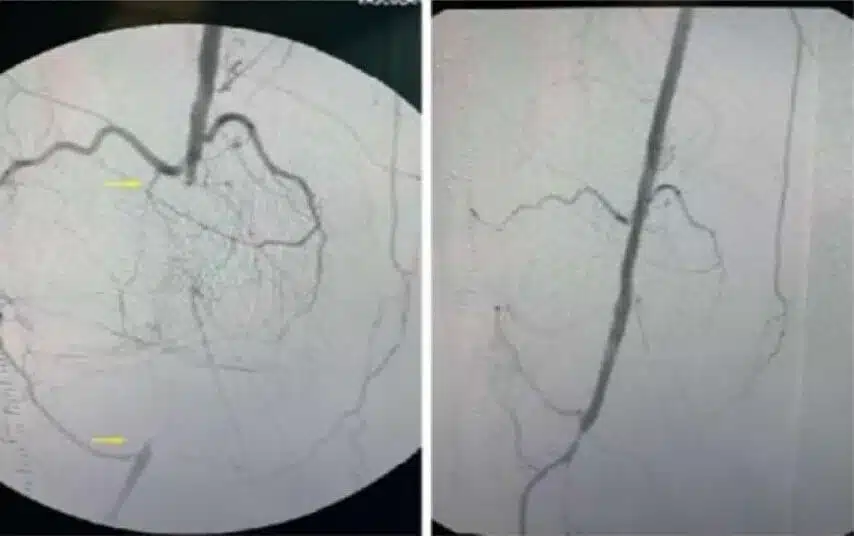

• Smoker with high blood pressure, hyperlipidemia; CAD with remote stents in the past and known abdominal aortic aneurysm

• Referred by podiatrist for non-healing ulcer of the left foot

• Angiogram shows severe iliac tortuosity; antegrade CFA access to occluded popliteal aneurysm; severe 3VD

• Wingman™ used to cross pop aneurysm; IVUS indicated thrombosis, DES stents dilation

• Restored 2-vessel runoff to foot